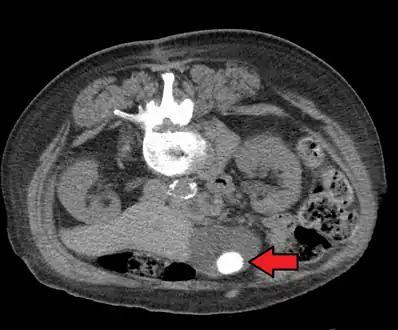

On abdominal ultrasound, sinking gallstones usually have posterior acoustic shadowing. In floating gallstones, reverberation echoes (or comet-tail artifact) is seen instead in a clinical condition called adenomyomatosis. Another sign is wall-echo-shadow (WES) triad (or double-arc shadow) which is also characteristic of gallstones.[40]

- A 1.9 cm gallstone impacted in the neck of the gallbladder and leading to cholecystitis as seen on ultrasound. There is 4 mm gall bladder wall thickening.

Large gallstone as seen on CT- A normal gallbladder on ultrasound with bowel peristalsis creating the false appearance of stones